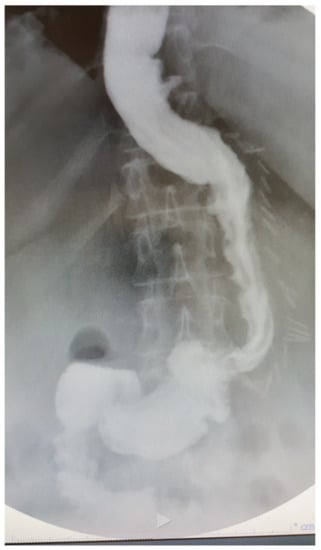

1.1. Gastric Diverticula and Sleeve Gastrectomy

1.2. Technical Considerations

- After the transoral position of a bougie (of diameter ranging 36–40 Fr), sleeve gastrectomy is performed with the use of a stapler, beginning from the distance of 4–6 cm from the pylorus up to the angle of His.

- The staple line should be regular and straight from the antrum to the angle of His.